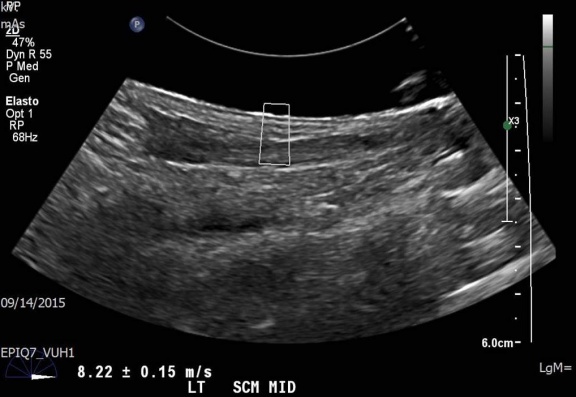

Over the course of the four-year study, they will accrue up to 100 patients with existing oropharyngeal cancer. Patients will undergo chemotherapy and radiation, and their results will be monitored every three months for a year using shear wave elastography (SWE) – a noninvasive ultrasound procedure that will identify stiffness in the fibrotic tissue.

“Our study is the first of its kind to assess the accuracy of a new type of sonographic evaluation for purposes of noninvasive evaluation of the skin and surrounding tissues, relative to side effects related to radiation therapy and chemotherapy of orofacial cancers,” said Arthur Fleischer, M.D., Professor of Radiology and Radiological Sciences and Ultrasound Imaging Medical Director. “SWE has been made possible by the development of both new transducer technology and software which can quantify changes in thickness and texture by calculating the velocities of the acoustic energy as it passes through soft tissue.”